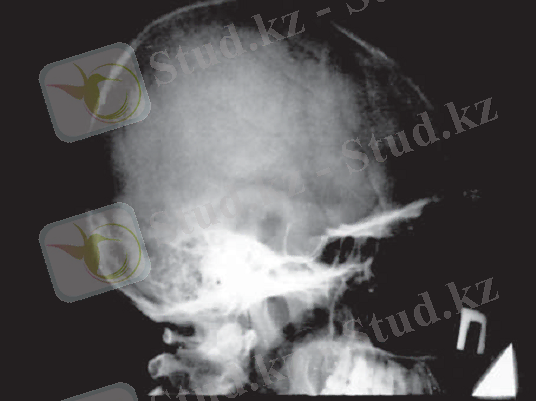

Гипофиздің интраселлярлы ісіктерінің рентгендиагностикасы түрік ершігінің өлшемдерін анықтауға негізделеді. Қалыпты жағдайда түрік ершігінің өлшемдері тең: сагиттальды - 12-15 мм, вертикальды- 8-9 мм (2. 2 сурет) .

2. 2 сурет. Рентгенкраниография:

а - түрік ершігінің рентгенографиялық бағдарлары;

б - қалыпты жағдайдағы түрік ершігінің рентгенограммасы

Гипофиздің үлкен аденомалары түрік ершігі өлшемдерінің үлғаюына, кіреберісінің кеңеюіне, сына тәрізді сүйек өсінділерінің жіңішкеріп, қысқаруына, түбінің тереңдеуіне, ершік арқасының бұзылуына, екі контурлы болуына (бір немесе екі кескіннің нақты болмауы) әкеледі, дегенмен бұл ешқандай диагностикалық қиындықтар тудырмайды (2. 3 сурет) . Түрік ершігінің шекарасынан аспайтын гипофиз микроаденомаларының рентгенограммаларында ешқандай өзгерістер анықталмайды.

Сурет 2. 3 . Гипофиз макроаденомасы кезіндегі бассүйек рентгенограммасы